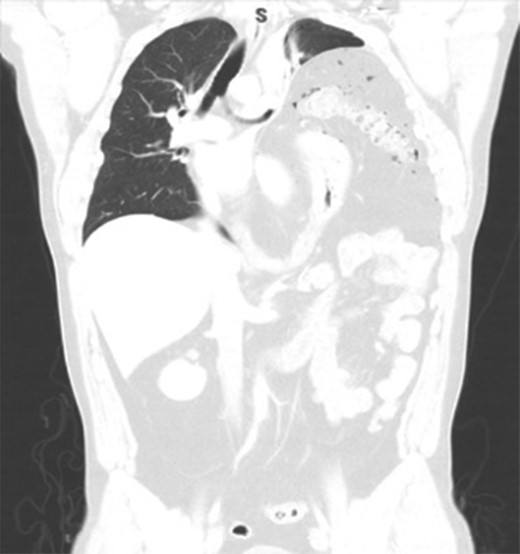

We present a 44-year-old male patient came to the emergency department complaining of right upper quadrant abdominal pain. The patient reported taking over-the-counter (OTC) ibuprofen intermittently for a past few months due to backaches. His past medical history is only positive for falling off a 15 feet ladder at the age of 15 years old. Upon examination, he had right upper quadrant abdominal tenderness, a heart rate of 90 beats/min and a respiratory rate of 20 breaths/min on room air. The patient clinical status was stable and looked well. Chest x-ray showed a moderate left hemidiaphragm elevation with bowel contents overlying the left chest (Fig. 1). Of note, a large amount of air inferior to the right hemidiaphragm was indicative for pneumoperitoneum. Laboratory investigations were immediately carried out and revealed a white blood cell count (WBC) of 4.5 × 109/L (normal range: 4–11 × 109/L). The WBC remained at the normal level until the end of the patient’s admission. Further imaging studies were ordered due to the peculiar coexistence of x-ray findings and stable clinical status. The computed tomography (CT) scan showed a contracted left lung with severe volume loss and just mild aeration of the left upper lung (Fig. 2). No definite left pneumothorax was seen. The majority of the left hemithorax was filled with abdominal contents including the stomach, spleen, pancreatic tail, left kidney, splenic flexure of the colon, and small bowel loops. A small hypodense focus was observed within the intra-thoracic stomach and extended to the stomach wall, with mild adjacent stranding of fat and a small amount of free fluid. We suspected the presence of perforated gastric ulcer secondary to non-steroidal anti-inflammatory drugs (NSAIDs) usage. The upper gastrointestinal (GI) series was performed and did not show any extravasation, indicating that there was some other source or the gastric perforation had walled off. The patient was thus managed conservatively; his diet was advanced and the patient discharged home on Day 4.

CT scan showing collapse of left lung and left diaphragmatic hernia.